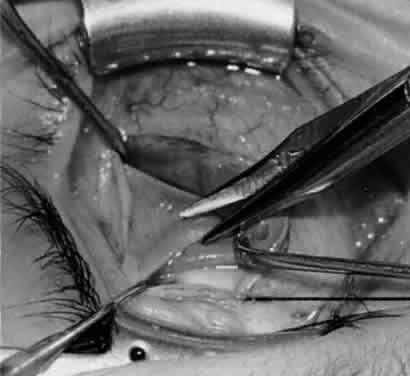

Fig. 5. The Stevens hook is placed adjacent to the posterior edge of the inferior oblique muscle and rotated as the inferior oblique muscle is drawn into the operative field. A forceps is used to retract the redundant Tenon's capsule, encapsulated fat, and intermuscular septum as the muscle is drawn further into the operative field with the Stevens muscle hook.

Fig. 6. The Westcott scissor is used to open the intermuscular septum along the posterior border of the inferior oblique muscle. Care is taken to cut adjacent to the tip of the Stevens muscle hook. This incision is important because it helps to avoid damaging the Tenon's capsule and releasing fat, which leads to the adherence syndrome and postoperative hypotropia.

Fig. 7. A Westcott scissor is used gently to open a space beneath the elevated inferior oblique muscle and allow placement of a Green muscle hook.